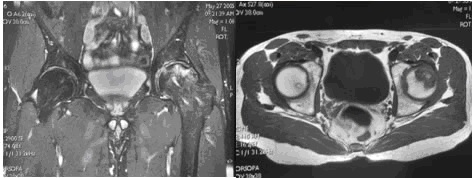

La risonanza magnetica è considerata la metodica d’indagine più accurata per quantificare l’area osteonecrotica in fase precoce e per individuare la sede topografica della lesione, con una sensibilità che oscilla fra 88 e 100 % grazie alle caratteristiche di multiplanarietà e multiparametricità. La RMN, infatti, valuta l’area interessata su 3 piani: trasversale, coronale sagittale ed, inoltre, permette di discriminare la componente ossea da quella cartilaginea, evidenziando un’eventuale condropatia.